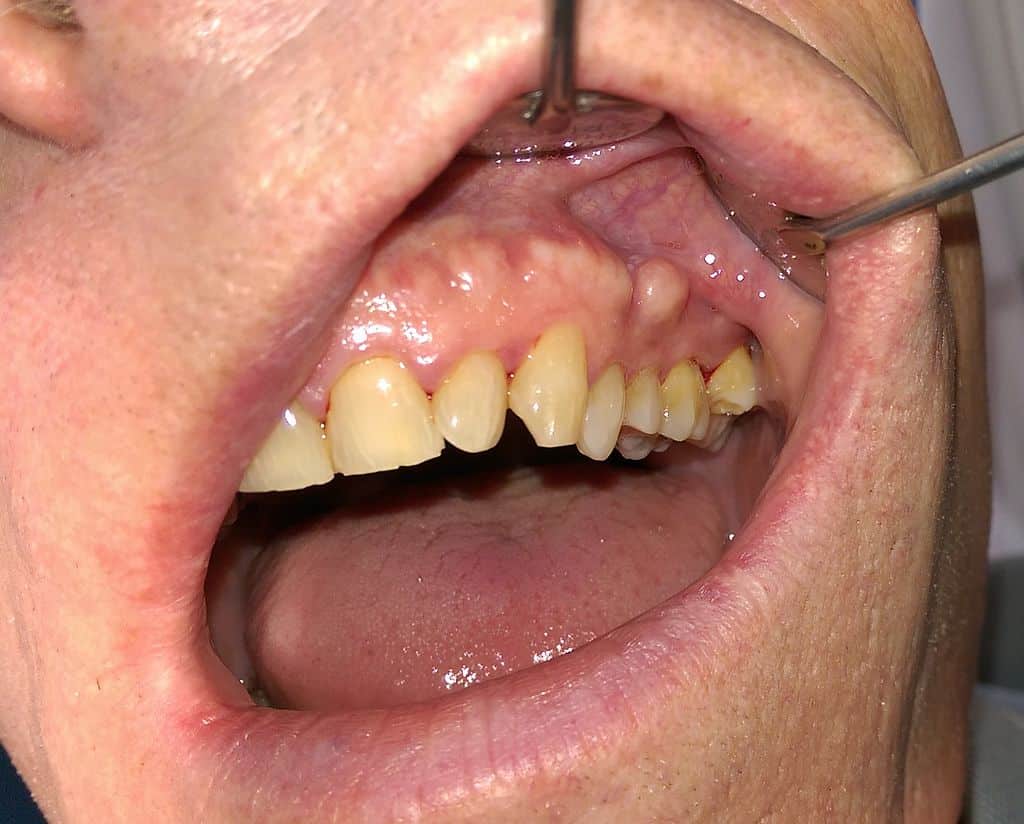

Matthew Ferguson 57, CC BY-SA 3.0 <https://creativecommons.org/licenses/by-sa/3.0>, via Wikimedia Commons

- Buccal exostosis: Bumps on the inside of the cheeks.

- Gingival exostosis: Growths on the gums.

- Alveolar ridge exostosis: Bony growths along the tooth-bearing areas.

In fact, most patients are unaware they even have tori or buccal exostoses until a dentist points them out. They rarely cause problems on their own, but their presence can become a major concern when dentures are needed. Large mandibular tori in particular may make it difficult — or even impossible — to comfortably wear a lower denture. In such cases, removal may be necessary before prosthetic treatment can proceed.